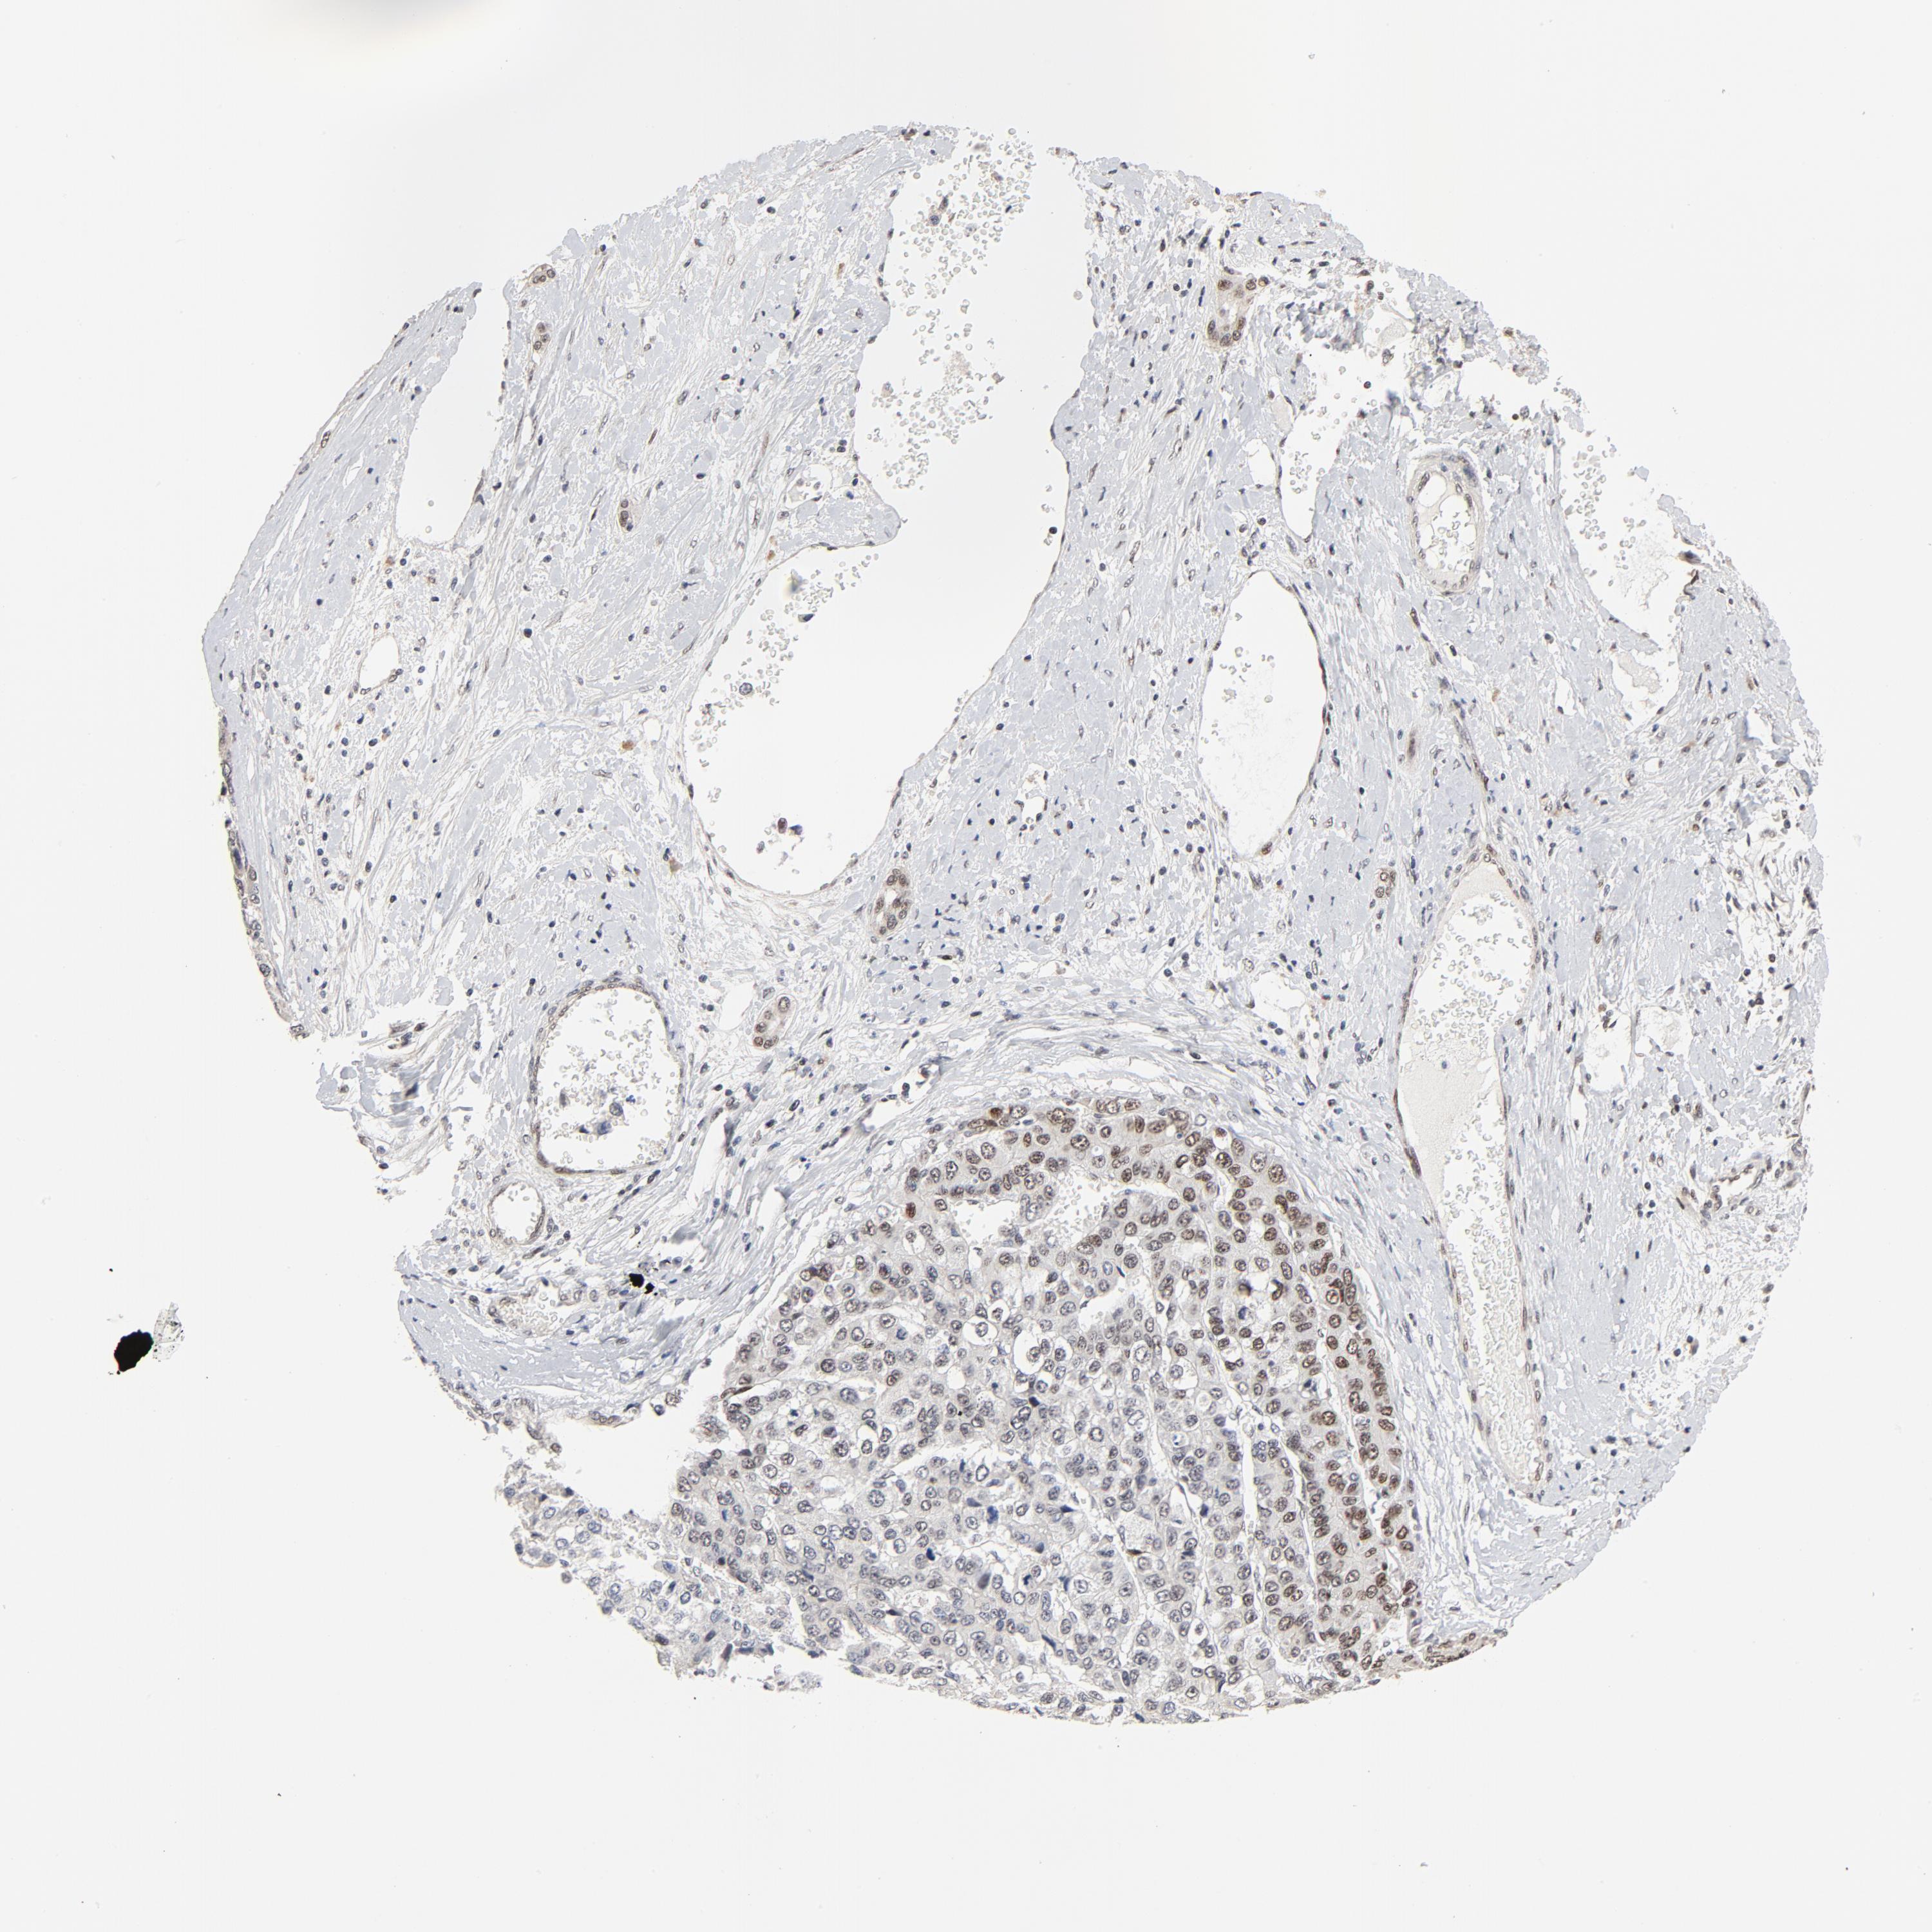

LIVER CANCER - Protein expressioni

A mouse-over function shows sample information and annotation data. Click on an image to view it in a full screen mode. Samples can be filtered based on level of antibody staining by selecting one or several of the following categories: high, medium, low and not detected. The assay and annotation is described here.

Note that samples used for immunohistochemistry by the Human Protein Atlas do not correspond to samples in the TCGA dataset.

Antibody stainingi

Antibody staining in the annotated cell types in the current human tissue is reported as not detected, low, medium, or high, based on conventional immunohistochemistry profiling in selected tissues. This score is based on the combination of the staining intensity and fraction of stained cells.

Each image is clickable and will lead to virtual microscopy that enables deeper exploration of all samples and also displays staining intensity scores, fraction scores and subcellular localization as well as patient and tissue information for each sample.

Antibody HPA026638

Antibody CAB004595

Staining

High

Medium

Low

Not detected

Intensity

Strong

Moderate

Weak

Negative

Quantity

>75%

75%-25%

<25%

None

Location

Nuclear

Cytoplasmic/membranous

Cytoplasmic/membranous,nuclear

Cholangiocarcinoma

Carcinoma, Hepatocellular, NOS